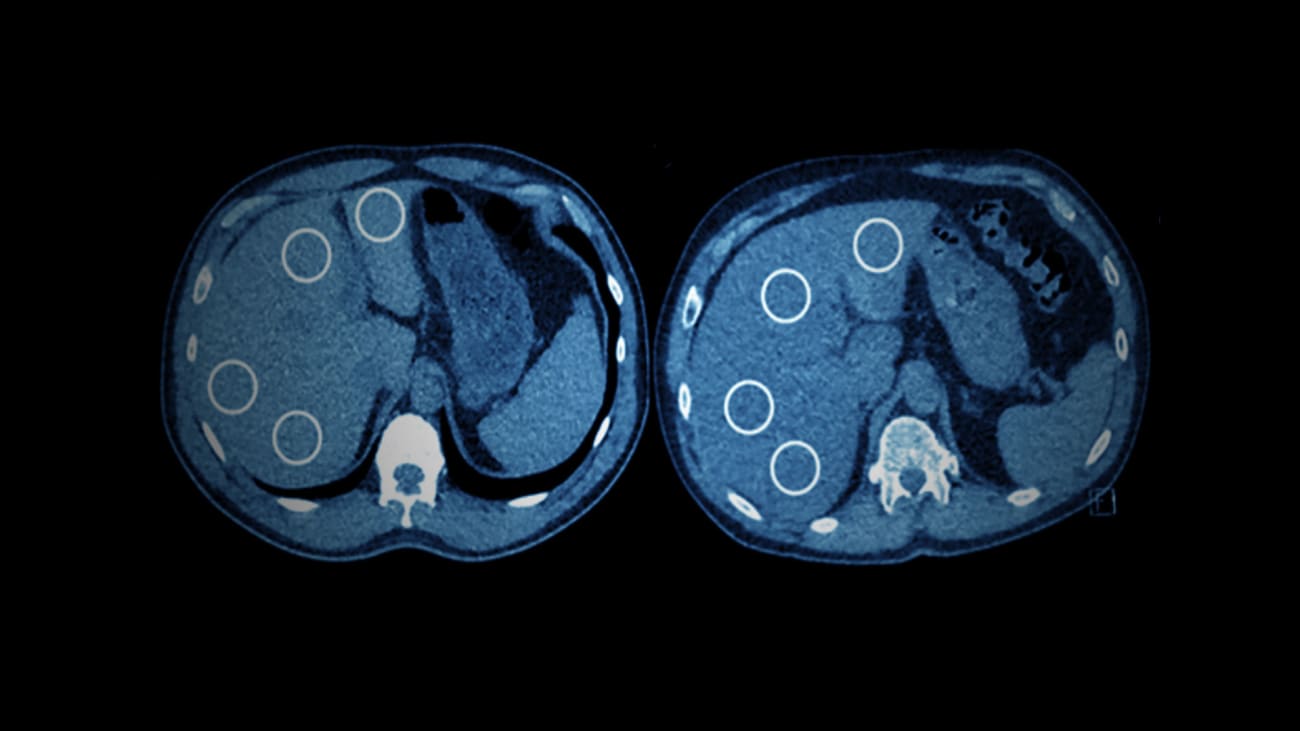

A known connection between liver disease and exposure to chemical toxins, such as benzene and glass fibers, prompted researchers at the Mount Sinai Health System in 2020 to investigate the incidence of hepatic steatosis—high levels of fat in the liver—in World Trade Center (WTC) first responders. Using low-dose CT (computed tomography) lung screening, the researchers found that the WTC cohort—composed of 154 individuals—was three times more likely to have moderate-to-severe steatosis than those who were not WTC first responders. Their findings, published April 2020, in Clinical Imaging, established this condition in WTC responders for the first time.